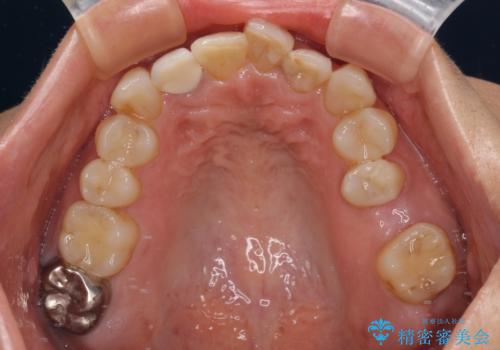

前歯のデコボコとむし歯治療の跡 インビザライン矯正とオールセラミッククラウン治療

- 前歯のセラミッククラウンの縁が見えることが気になってから、デコボコも気になるようになってきたとのことで来院された患者様です。

デコボコの程度は中等度であったため、インビザライン・モデレートパッケージにて歯列を整えることとしました。

セラミッククラウンの装着されていた前歯と、大きな修復治療の跡がある反対側の歯は、矯正治療後に補綴治療を行うこととしました。

奥歯の欠損はインプラント、ブリッジ、入れ歯のどれにすれば良いかを決められず、仕事が非常にお忙しいこともあり、保留としたまま治療を終えることとなりました。

後戻りのリスクがあるため、なるべく早めに欠損補綴治療を開始する予定です。